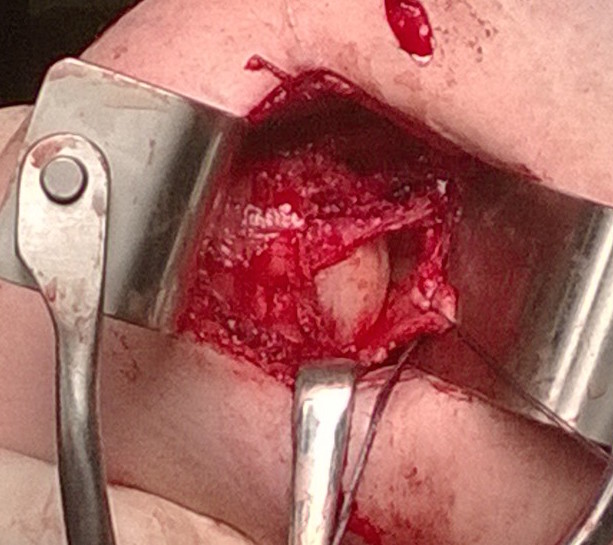

Open Anterior and Posterior Capsular shift

Open Antero - Inferior Capsular Shift +/- allograft reconstruction +/- subscapularis shift / Putti-Platt

Technique

Principle

- detach capsule from neck of humerus

- shift capsule superiorly to obliterate the inferior pouch and decrease joint volume

Deltopectoral approach

- split subscapularis

- can perform subscapularis tenotomy and later tighten / Putti Platt

- T shape capsulotomy of capsule

- vertical component on articular margin humeral insertion all the way posterior

- transverse component to midpoint glenoid making superior and inferior flaps

- superior advancement inferior capsular flap

- eliminate inferior pouch and reduce posterior capsular redundancy

- then suture down superior flap

+/- allograft reconstruction

+/- subscapularis shift / Putti-Platt

Open capsular plication

Open anterior capsular plication with subscapularis tenotomy and lateral advancement / Putti Platt